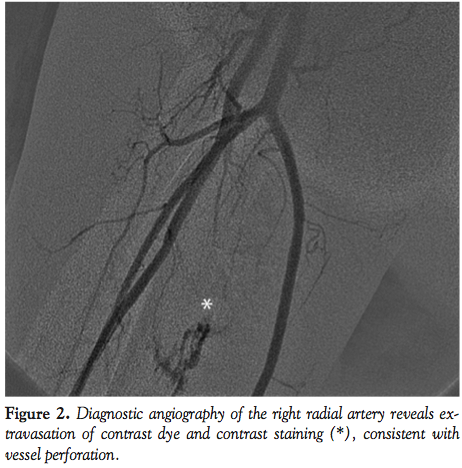

was begun, and a 6 Fr radial-specific diagnostic catheter (Tiger catheter, 6 Fr, 100 cm length; Terumo Medical Corporation) was guided to the ascending aorta by an angled tip hydrophilic wire (Stiff Angled Glidewire, 0.35 cm diameter, 145 cm length; Terumo Medical Corporation). Left coronary artery injection revealed in-segment restenoses of the proximal and mid portions of the left anterior descending artery (LAD), as well as severe obstructive disease at the origin of the first obtuse marginal branch (OM1) of the left circumflex artery (LCX) and ramus intermedius artery (RI) (Figure 1). The right coronary artery demonstrated mild diffuse disease throughout. He underwent PCI of the mid LAD, RI, and OM1 vessels. The diagnostic catheter was exchanged for a guiding catheter (Mach 1 FCL 3.5, 6 Fr; Boston Scientific) over a 300-cm long, 0.035-cm diameter J-tip wire. Adjunctive anticoagulation therapy was administered with a standard, weight-based bivalirudin bolus and infusion, and prasugrel was given orally. Activated clotting time was 352 seconds at 5 minutes after bivalirudin injection. Successful PCI was performed with deployment of a DES in the RI and percutaneous transluminal coronary angioplasty (PTCA) of the OM1 and LAD lesions.